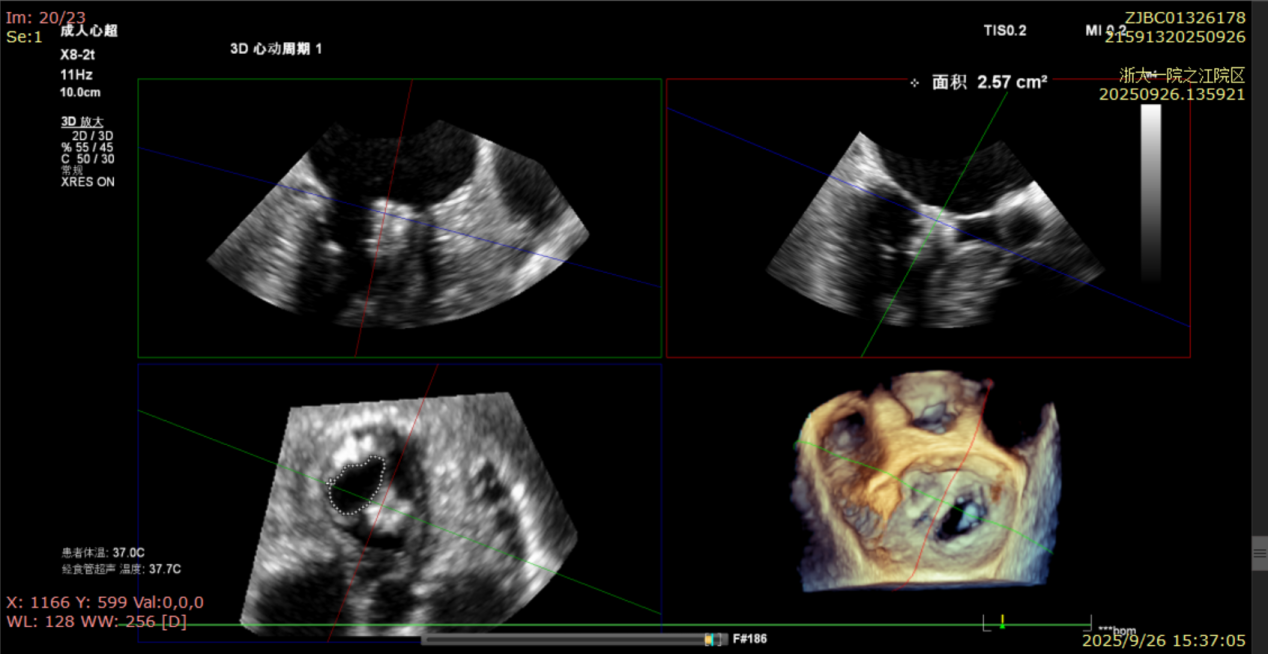

术后即刻反流降为少量,剩余瓣口面积2.57cm²,平均跨瓣压差2mmHg。